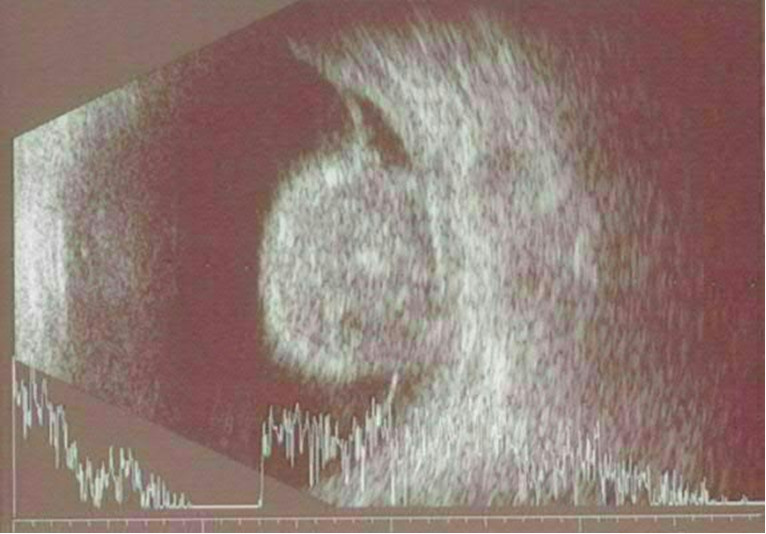

U pacjenta z nieprzejrzystymi ośrodkami optycznymi wykonano badanie USG. Jakiej jednostce chorobowej odpowiada poniższy obraz badania USG w projekcji A i B?